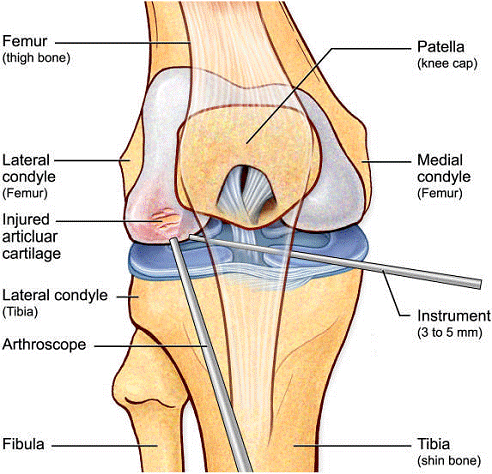

Artroscopia este o investigatie

invaziva care permite vizualizarea foarte buna a spatiului articular cu

ajutorulul artroscopului. Artroscopul este format dintr-un endoscop cu fibra optica, instrument care se introduce direct

in articulatie printr-o mica incizie subcutanata. Artroscopia ofera medicului posibilitatea

de a inspecta suprafetele articulare si tesutul moale din jur: ligamentele si cartilajele.

Introducerea instrumentelor endoscopice permite nu numai examinarea in scop

diagnostic a interiorului articulatiei, dar si tratarea leziunilor articulare

sau indepartarea corpilor straini liberi din spatiul articular, fara a

traumatiza sever tesuturile invecinate, cat si urmarirea evolutiei unei

afectiuni articulare sau monitorizarea eficientei tratamentului.

Dupa o deschidere minima a articulatiei, practicata sub anestezie locala, medicul introduce artroscopul, tubul rigid dotat cu aparatura optica si instrumentele care permit realizarea chirurgiei intraarticulare. Majoritatea componentelor articulatiei sunt accesibile sub artroscopie: un corp strain articulatiei poate fi indepartat, un cartilaj - remodelat, iar un menisc - recusut sau scos. In sfarsit, ligamentele pot face obiectul unor acte chirurgicale directe.

Un diagnostic de rutina de artroscopie este utilizat pentru a evolua toate compartimentele intra-articulare ale genunchiului. Inainte de efectuarea microfracturii, se raporteaza orice patologie intra-articulara asociata (cum ar fi de menisc).